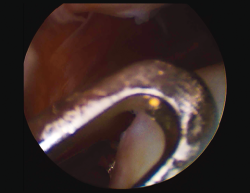

8. The membrane is placed in the lesion and the margins of the former are sutured to the healthy cartilage with Vicryl® 5/0 (Figures 11 and 12).

9. We check that the membrane is well fixed and seal between the stitches with Tissucol® (Figure 13). A waiting period of 3-5 minutes is observed, and the joint is mobilized before closure to check that the membrane does not detach with movement of the joint.